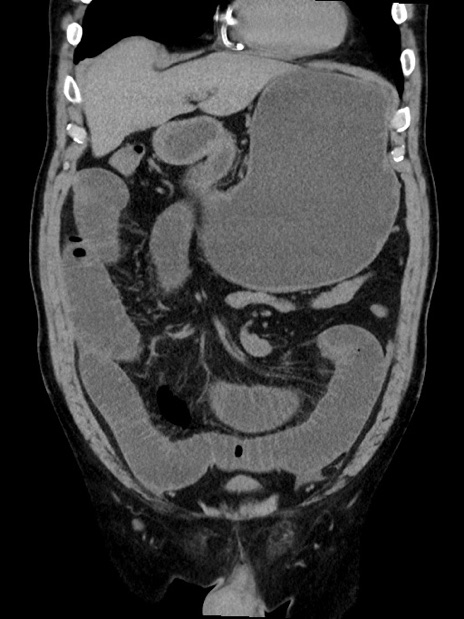

症例35(冠状断像)

【症例】70歳代 男性

【主訴】腹部膨満、嘔吐

【現病歴】昨日より腹部膨満感出現。本日増悪し、仙痛出現。嘔吐あり、受診。

【既往歴】糖尿病、胆摘後

【身体所見】BP 149/80mmHg、HR 74/min、BT 35.9℃、腹部:膨満、軟、圧痛なし。腸雑音減弱あり。上腹部正中切開瘢痕あり。

【データ】WBC 13500、CRP 1.72